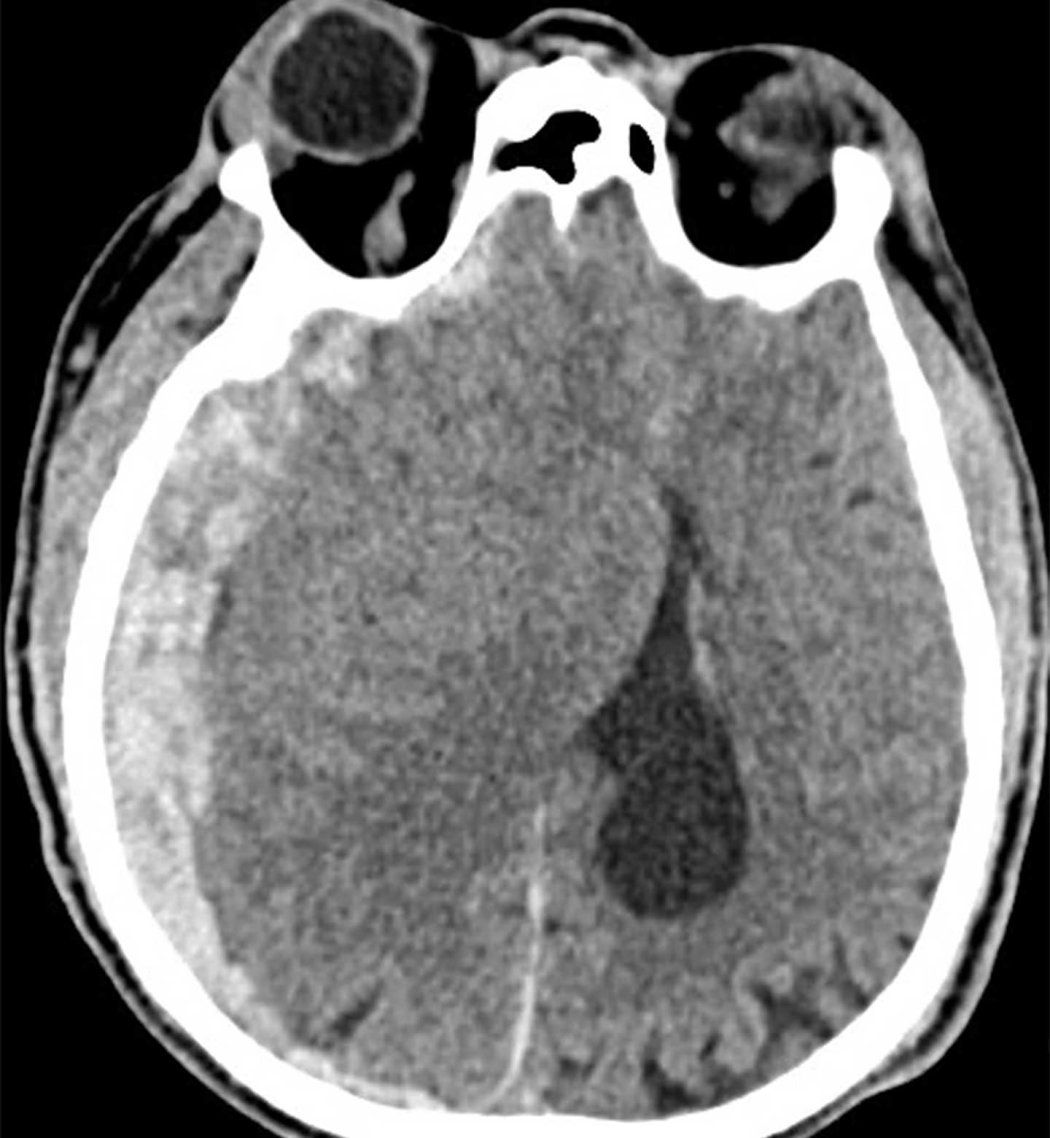

A CT scan of a traumatic brain injury.

CT scan of an older patient with subdural hematoma, a bleed near the brain, which is more common in people over 65 due to normal brain shrinkage that puts pressure on weakened veins. The patient acquired this injury after a ground-level fall.